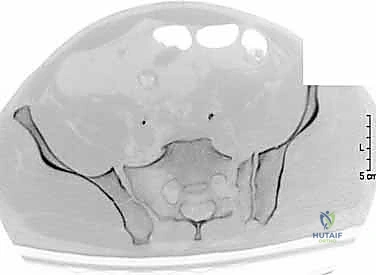

2. الأشعة السينية (X-rays): توفر نظرة أولية سريعة على كسور الحوض (AP, Inlet, and Outlet views).

3. التصوير المقطعي المحوسب (CT Scan): وهو المعيار الذهبي (Gold Standard) لتشخيص كسور الحوض والعجز. يقوم الدكتور هطيف باستخدام تقنية إعادة البناء ثلاثي الأبعاد (3D Reconstruction) لفهم هندسة الكسر بدقة متناهية قبل الدخول إلى غرفة العمليات.